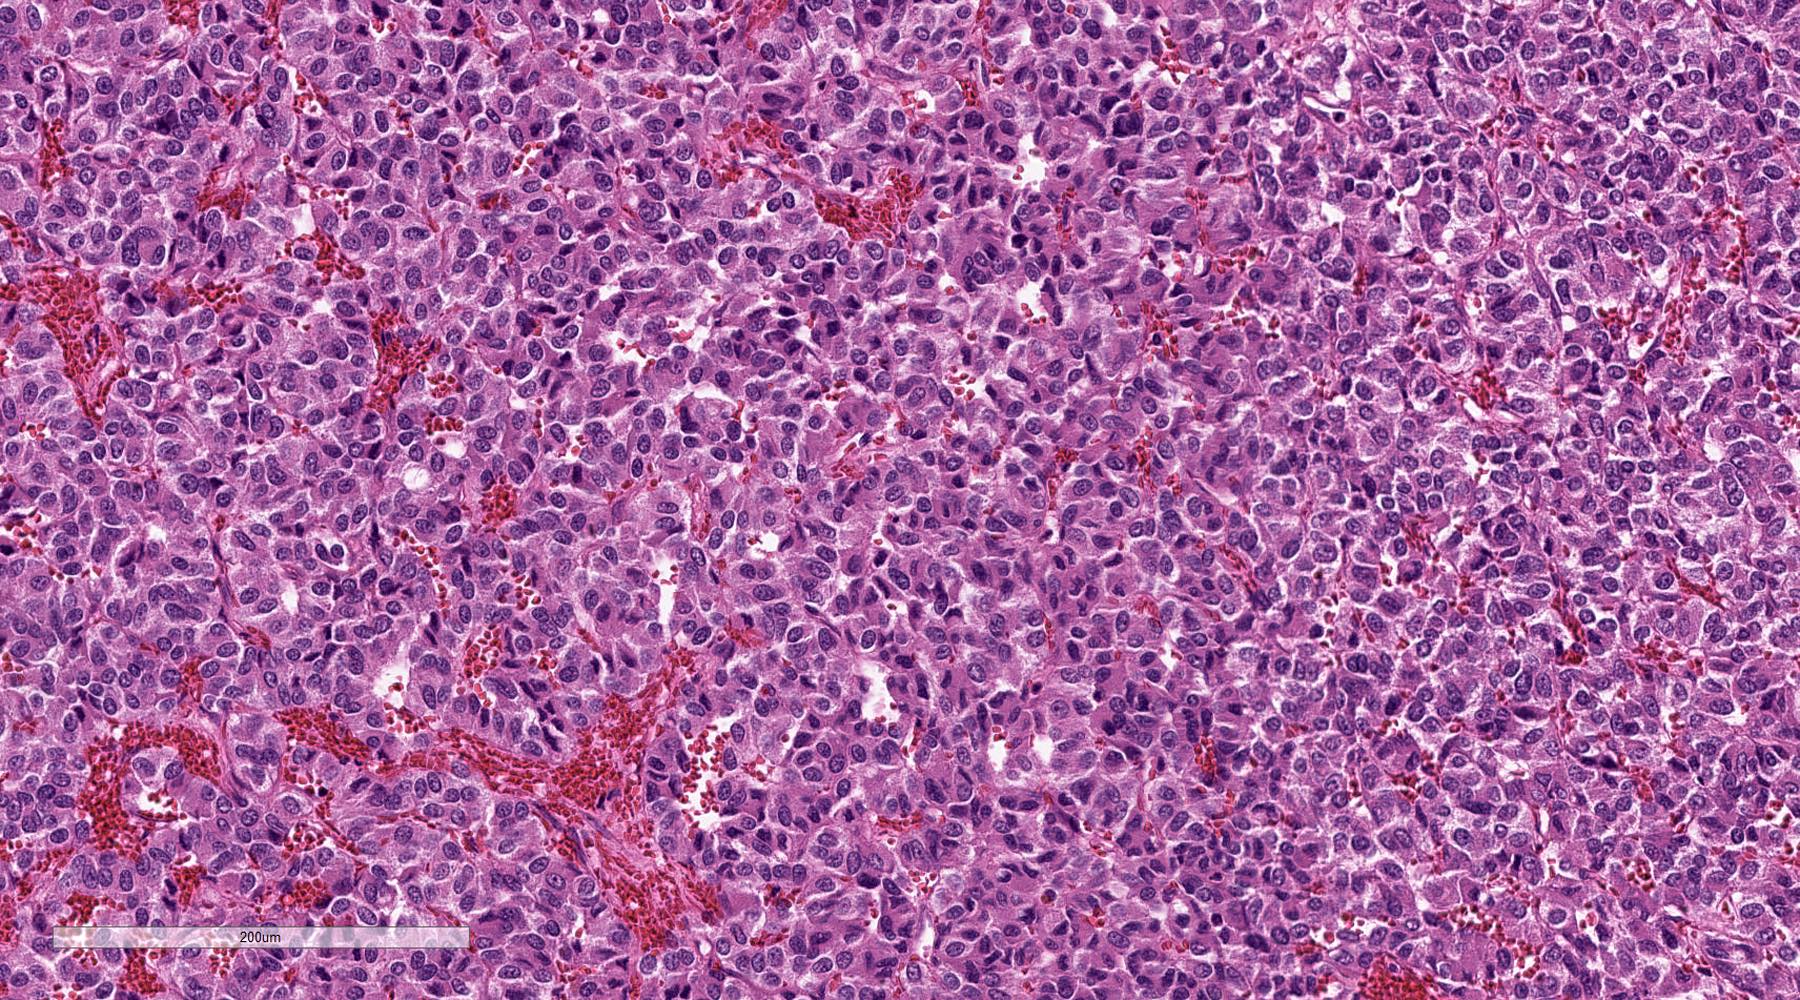

Microscopic (histologic) description

- Prevailing histologic pattern: epithelioid chief cells arranged in distinctive clusters / nests (zellballen pattern), separated by prominent fibrovascular stroma (J Clin Med 2018;7:280)

- Trabecular pattern: ribbons or cords of epithelioid cells divided by fibrous bands

- Other patterns: pseudorosette, angioma-like, spindled and sclerosing

- Chief cells: round, oval to polygonal cells with abundant granular basophilic, eosinophilic or amphophilic cytoplasm (Surg Pathol Clin 2019;12:951)

- Scattered ganglion cells can be seen

- No or rare mitotic figures except in highly aggressive rapidly proliferating lesions

- May have focal chronic inflammatory infiltrate

Microscopic (histologic) images

Contributed by Luvy Delfin, M.D. and Sylvia L. Asa, M.D., Ph.D.